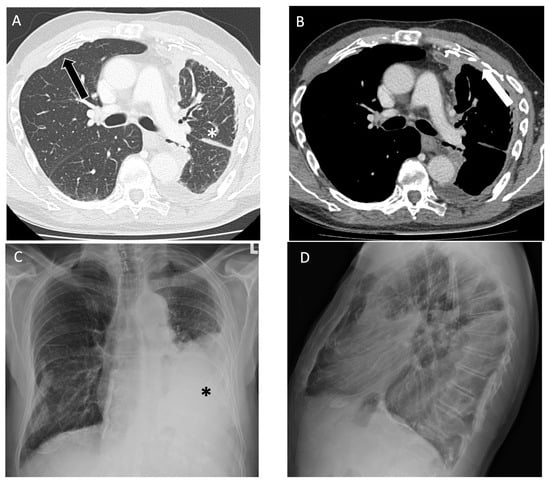

Figure 4.

An 89-year-old non-smoking male with asbestos exposure from construction work, diagnosed with epithelioid mesothelioma, later confirmed on video-assisted thoracoscopic surgery biopsy. (A) On axial computed tomography, there is a partly calcified pleural plaque anteriorly on the right (black arrow) and volume loss in the left lung (asterisks) related to a rind of pleural thickening; (B) on the left, the rind of pleural thickening (arrow) has a nodular appearance consistent with mesothelioma and there is a small pleural effusion after thoracentesis that drained 1.2 L of fluid; follow-up (C) posteroanterior and (D) lateral view radiographs one week later demonstrate a reaccumulated moderate-to-large size pleural effusion opacifying the left mid-to-lower lung zone (asterisks).